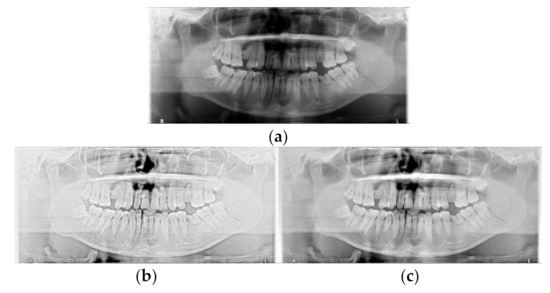

2.2.1. Data Augmentation